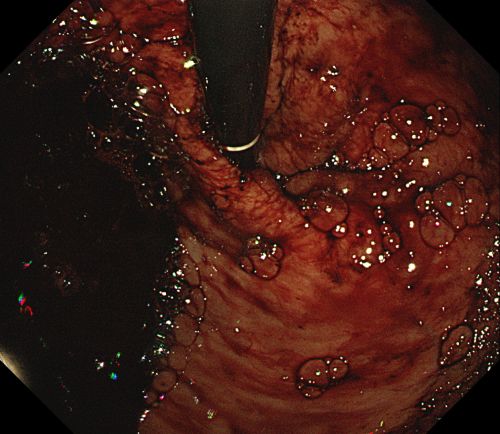

内镜下进行食管静脉曲张硬化剂注射治疗。

患者旋即被推入手术室,麻醉三科刘际童主任为其进行气管插管、全麻,保持呼吸道通畅,并进行中心静脉置管等维持血压平稳。综合内科彭娅主任进行胃镜治疗,发现患者重度食管静脉曲张,胃底可见大量血液及血凝块;小心翼翼抽吸血液及清洗血块后,寻找到“犯罪血管”,在内镜下进行食管静脉曲张套扎+硬化剂注射治疗,封闭出血血管。